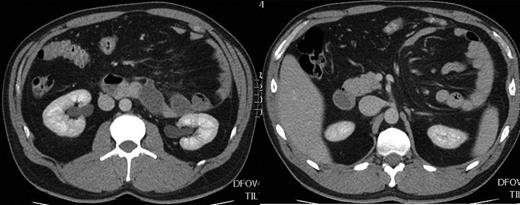

Hasson's insufflations technique was used for an initial infra-umbilical port insertion. Two further operating ports were place in the right lower quadrant under direct vision. Laparoscopy confirmed the radiological findings; the majority of the small intestine was found to lie inside the paraduodenal hernial sac. The sac lay behind the mesentery of the descending colon extending cranially behind the transverse colon and splenic flexure and lesser sac in front of the structures of the left retro-peritoneum. The neck of the hernia neck was formed anteriorly by free edge of descending colonic mesentery containing inferior mesenteric vein and posteriorly by retro-peritoneum. The neck lay to the left and caudal to the duodeno-jejunal junction with the ligament of Treitz fusing with the superior boarder. The proximal Jejunum directly distal to the DJ flexure entered the sac, the terminal ileum was identified within the abdomen, the caecum lay in the right iliac fossa, the remainder of the small intestine was within the hernia (Fig. 2 1 and 2). There were peritoneal adhesions at the neck of the hernia to the viscera entering the sac which prevented spontaneous reduction. Operative reduction of the hernia commenced with sharp dissection of these adhesions, followed by sharp and blunt dissection, the neck of the sac was cleared and mobilized. Once this procedure was complete the small intestine was easily reduced to the abdominal cavity, occasional adhesions to the hernial sac were divided to complete this process (Fig. 2 3 and 4). The hernial neck was closed with a continuous suture opposing the peritoneum of the free boarder of the descending colonic mesentery to the peritoneum below the D-J flexure to the left of the aorta. Post-operative recovery was uncomplicated and discharge was within 23 h. The patient made good recovery and to date has had no recurrence of symptoms over 3 years of follow-up.

(1–4) Identification and laparoscopic reduction of paraduodenal hernia in the sequence.